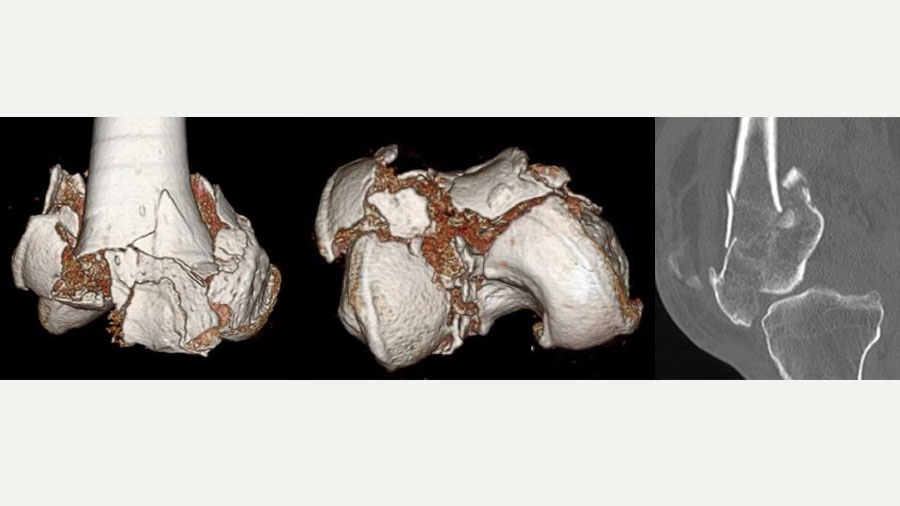

The complexity of the injury required a structured, multi-step approach, starting with comprehensive imaging. While X-rays provided an initial overview, it was the CT scan that delivered the critical 3D visualization of the fracture pattern. This enabled precise identification of each fragment and helped enormously in preoperative planning.

Such advanced imaging is essential for joint injuries where the accuracy of reduction dictates functional outcome. It allowed me to mentally reconstruct the knee and consider the tools and implants I would need. A detailed plan was then developed with contingencies in place—Plan B, and Plan C etc—including alternatives for fixation devices that might not conform to standard knee fracture patterns.